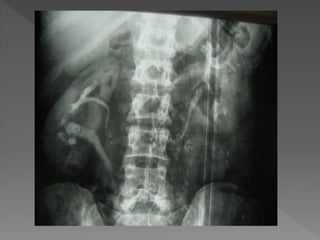

 The plain film demonstrates

 The plainfilm demonstrates calcification within distended upper pole calyces